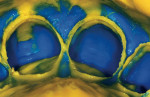

A two-cord impression technique can be used to capture most master impressions for full coverage (circumcoronal) and facial veneer restorations with both intracrevicular and equicrevicular margins (at the free gingival margin). First, a #0 cord (GingiBRAID 0a, Dux Dental, Oxnard, CA) is packed around each preparation margin starting from the lingual-proximal to the facial aspect, then back through the remaining proximal area to the lingual aspect (Figure 1). The excess at both lingual ends is trimmed, and the ends of the cord are tucked into the lingual gingival sulcus so that the ends butt against one another. For a facial veneer preparation, the retraction cord is packed through the proximal aspect toward the lingual proximal line angle where the excess cord is cut and the remaining end is tucked into the gingival sulcus. If desired, the cords may be soaked in a hemostatic solution (Styptin, Dux Dental) and dried with a 2 x 2 roll before placement, or soaked after placement (Figure 2). Next, a #1 cord (GingiBRAID 1a, Dux Dental) is placed on top of the #0 cord in the same fashion (Figure 3 and Figure 4). The preparation is cleansed with dentin desensitizer, AcquaSeal Dentin Desensitizer (AcquaMed™ Technologies, Inc, Batavia, IL), on a cotton pledget. When ready, the #1 cord is teased out of the sulcus using an explorer (Figure 5) from the facial aspect of each preparation and the amount of retraction is evaluated. The impression should capture not only the entire restorative margin but also about 0.5 mm of the tooth-root surface apical to the margin. If the marginal gingiva adjacent to any restorative margin rebounds to contact the tooth/margin, a small piece of a larger diameter cord (#2) should be placed into the affected area for an additional minute and then removed. This added retraction should be sufficient to create a space between the tooth surface and the inner lining of the gingival sulcus. The goal of retraction is to “create a moat (space in which to inject light-bodied impression material) around the castle (tooth preparation)” (Figure 6). To capture a precision impression, light-bodied impression material should be injected not only around the prepared teeth but also over all occlusal and incisal surfaces so that the stone models can be accurately articulated. The impression tray with the heavy-bodied impression material is then placed in the mouth for the appropriate time based on the manufacturer’s recommendations. When inspecting the master impression, all preparation margins should be readily visible and a cuff of impression material must appear around all marginal areas (Figure 7). This will help to ensure proper marginal trimming of dies by the laboratory and correct restorative emergence profiles.